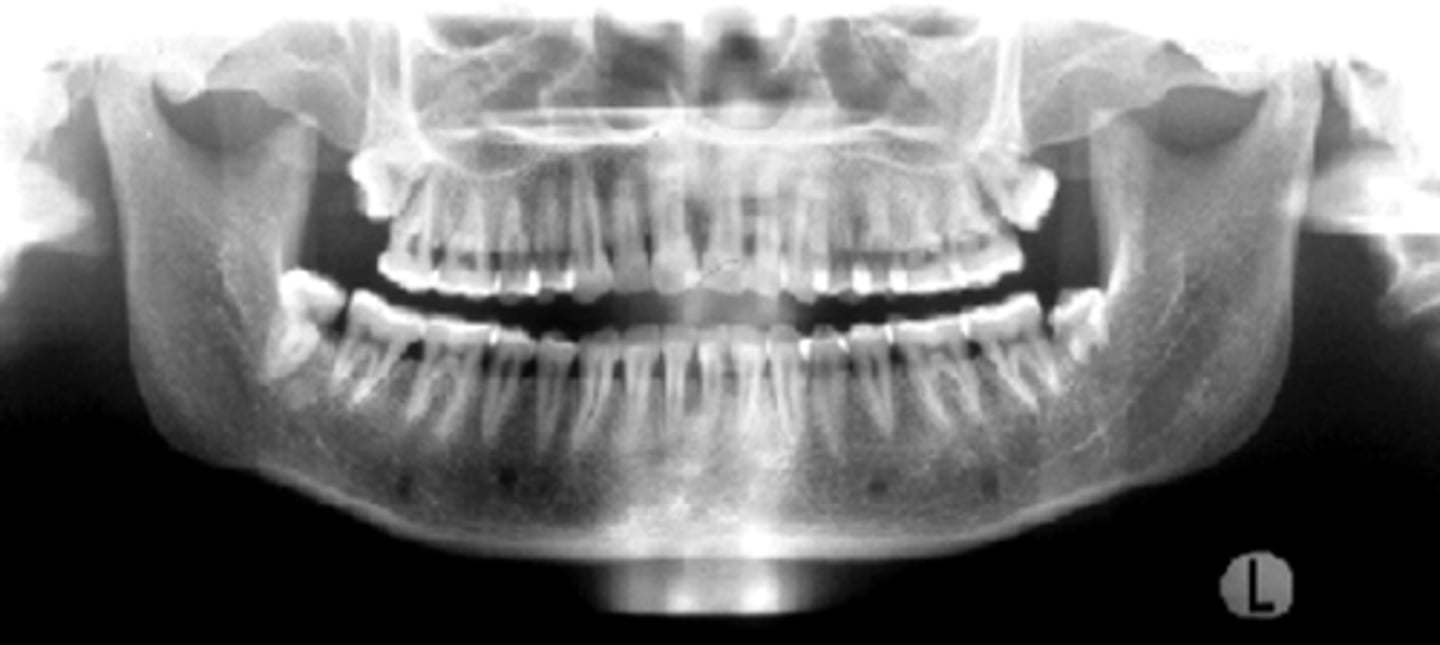

none - ideal

ID the positional error from the radiograph: